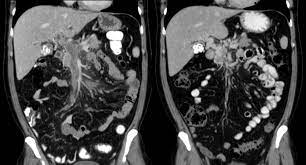

3. 신경영상검사(Neuroimaging): 뇌의 혈관 상태를 평가하기 위해 다양한 신경영상 검사가 사용됩니다. 주로 사용되는 검사에는 다음이 포함됩니다:

- CT 스캔(Computed Tomography): CT 스캔을 통해 뇌 혈관의 형태와 혈류를 시각화할 수 있습니다.

- MRI(Magnetic Resonance Imaging): MRI를 사용하여 뇌혈관을 자세하게 평가하고 혈류 문제를 확인할 수 있습니다.

- 혈관조영술(Cerebral Angiography): 혈관조영술은 혈관 내부 구조를 자세하게 시각화하기 위해 사용됩니다. 이 절차는 모야모야병을 진단하는 가장 확실한 방법 중 하나입니다.